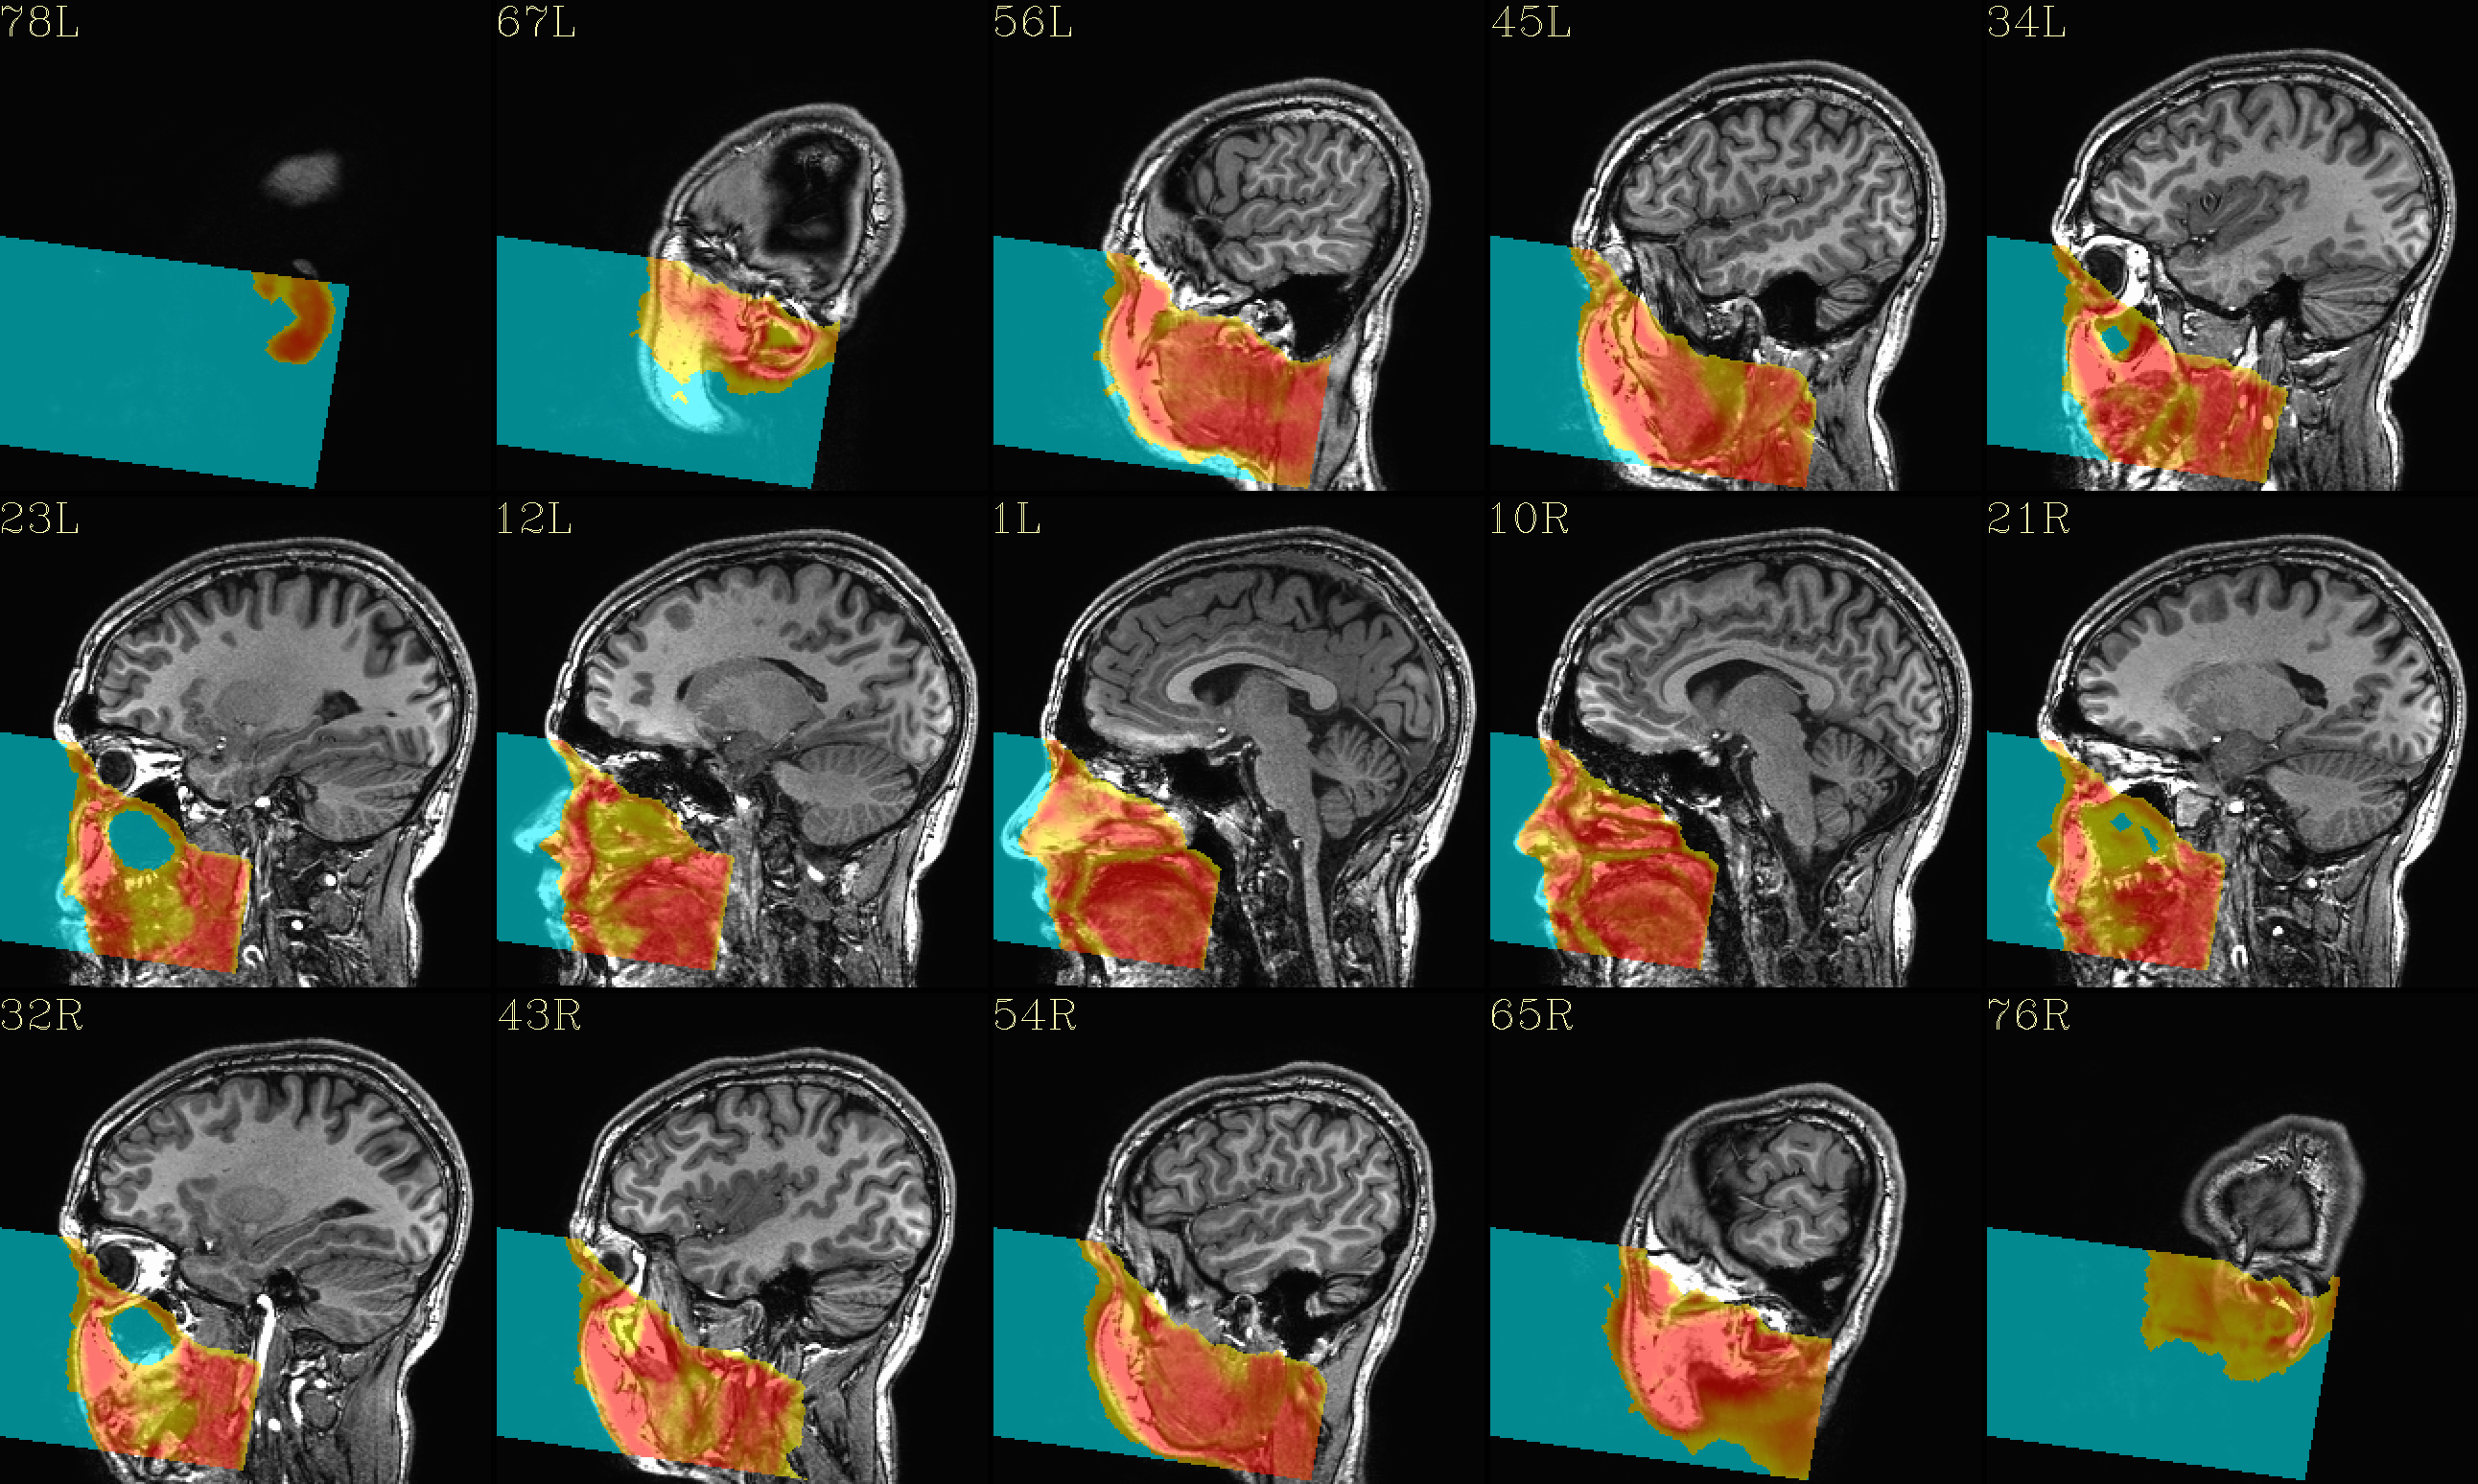

QC image files are produced in sets of 3: one each of axial, coronal and sagittal slices. They display the face and/or face_plus regions used, as well as the new dataset overlayed on the original, for comparison.

The output images of the above command are presented here. Based on

the prefix given, they would each be created in a subdirectory called

anat_QC.

The ‘face’ region for replacement or zeroing (overlayed on orig input) |

The ‘reface’ volume, overlayed on orig input |

|

The ‘face_plus’ region for replacement (overlayed on orig input) |

The ‘reface_plus’ volume, overlayed on orig input |